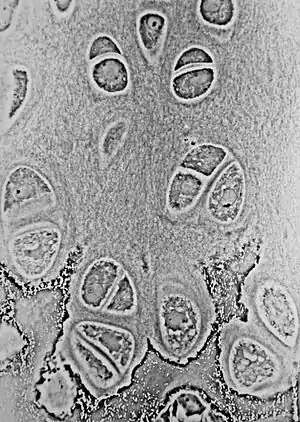

![]() Light micrograph of an undecalcified epiphyseal plate that is displaying the hypertrophic zone with its typical chondrocytes, matrix and three zones: maturation (top), degenerative (middle) and provisional calcification (bottom). | |

The growth plate has a very specific morphology in having a zonal arrangement as follows:[8]

| Epiphyseal plate zone (from epiphysis to diaphysis) | Description |

|---|---|

| Zone of reserve | Quiescent chondrocytes are found at the epiphyseal end |

| Zone of proliferation | Chondrocytes undergo rapid mitosis under influence of growth hormone |

| Zone of maturation and hypertrophy | Chondrocytes stop mitosis, and begin to hypertrophy by accumulating glycogen, lipids, and alkaline phosphatase |

| Zone of calcification | Chondrocytes undergo apoptosis. Cartilagenous matrix begins to calcify. |

| Zone of ossification | Osteoclasts and osteoblasts from the diaphyseal side break down the calcified cartilage and replace with mineralized bone tissue. |